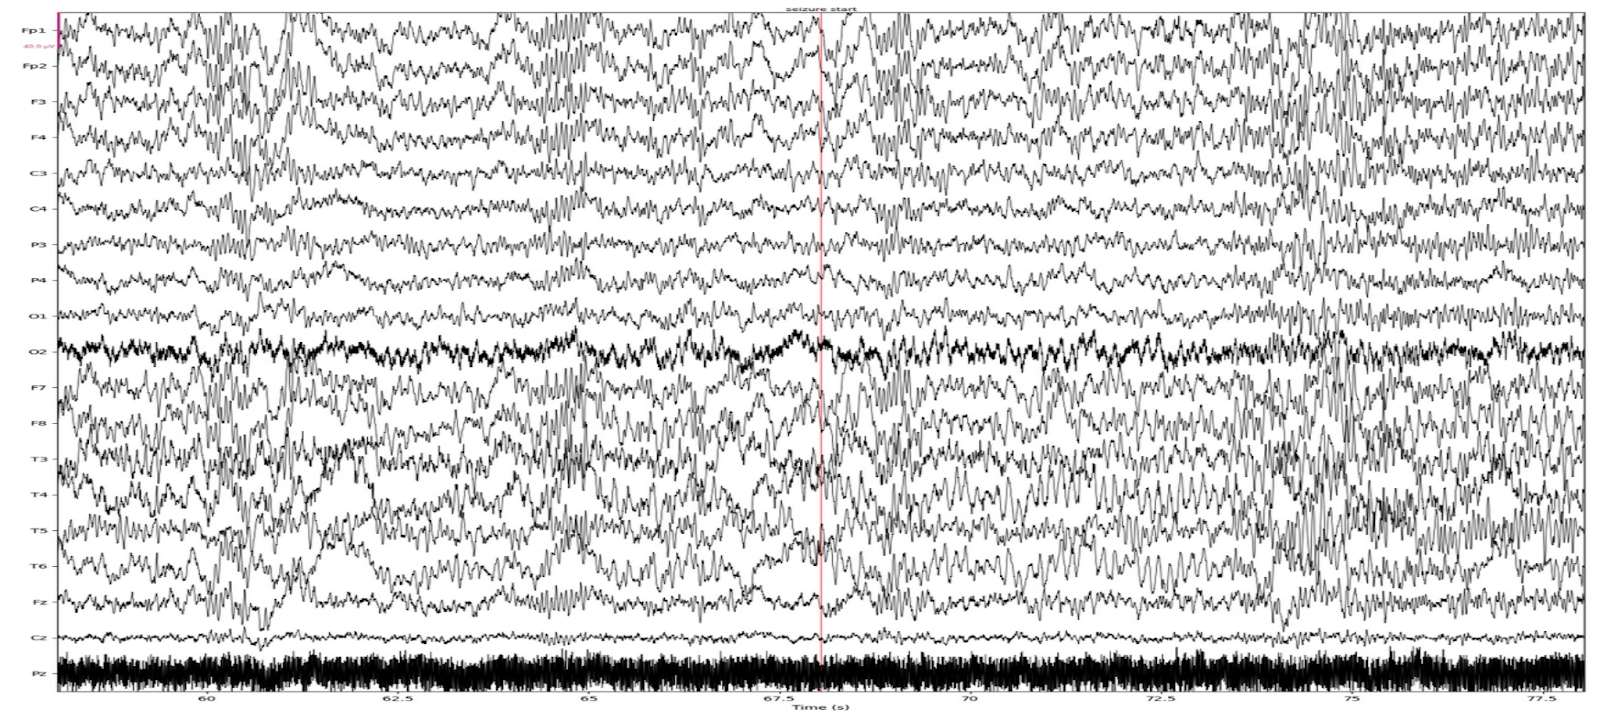

При записи получаются сигналы такого вида: